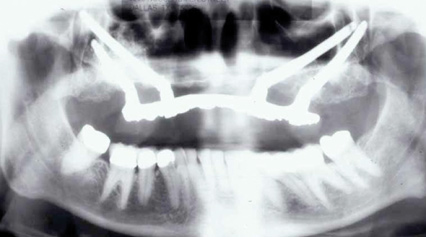

Fig 6. Panoramic radiograph of 56-year-old patient illustrating a number of dental procedures historically.

Figure 6

Interceptive implant therapy may then become a consideration earlier in life to create restorations that will not be subject to the latent effect of dental caries as aging continues. An example is shown in Figure 6 and Figure 7; the panoramic film of a 56-year-old man shows several orthognathic and extensive dental procedures historically. All full-coverage restorations had been replaced for a second time, and, again, all evidenced recurrent caries, but the existing dentition was periodontally sound and relatively esthetic.

The choice of removing a caries-challenged but restorable dentition at a younger age is ethically complex. Ultimately, the decision is the patient's alone based on informed consent of all available options. The removal of a potential lifetime of caries activity that is now more predictable than ever may be a viable option for this high-risk segment of a younger patient base.